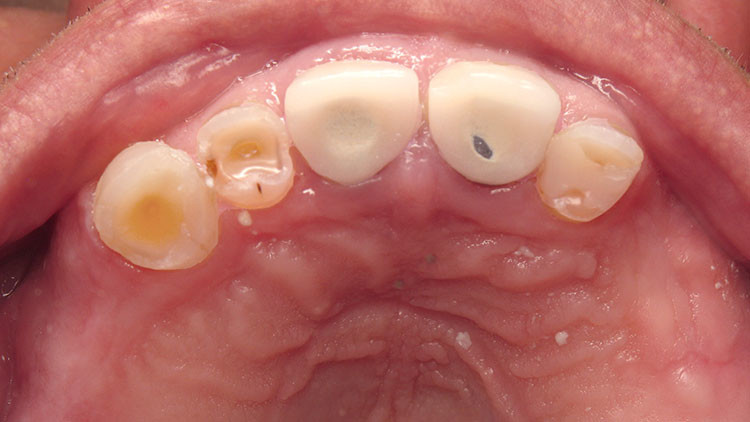

Occlusal hypervigilance can take a number of forms. Some patients become exquisitely sensitive about the way their teeth meet to the extent that they are better at detecting interferences than many dentists. These patients appear to have an amplified level of sensation which can be troublesome when perceived as pain. Nevertheless, unlike the princess and the pea, there is often a heavy occlusal contact present — you just need to know how to look for it and adjust it. A pitfall of not recognising such a patient is unnecessary root canal treatment.

Patients who have 'phantom bite' are also hypervigilant over the way their teeth meet, but these patients do not respond well to occlusal adjustment. Indeed it can be difficult to match the patient's symptoms to the findings of the occlusal examination. These patients often travel in vain from one dentist to another in search of a solution. The unwary dentist may fall into the trap of adjusting the patient's teeth but after an initial improvement the condition worsens as does the patient's hostility.